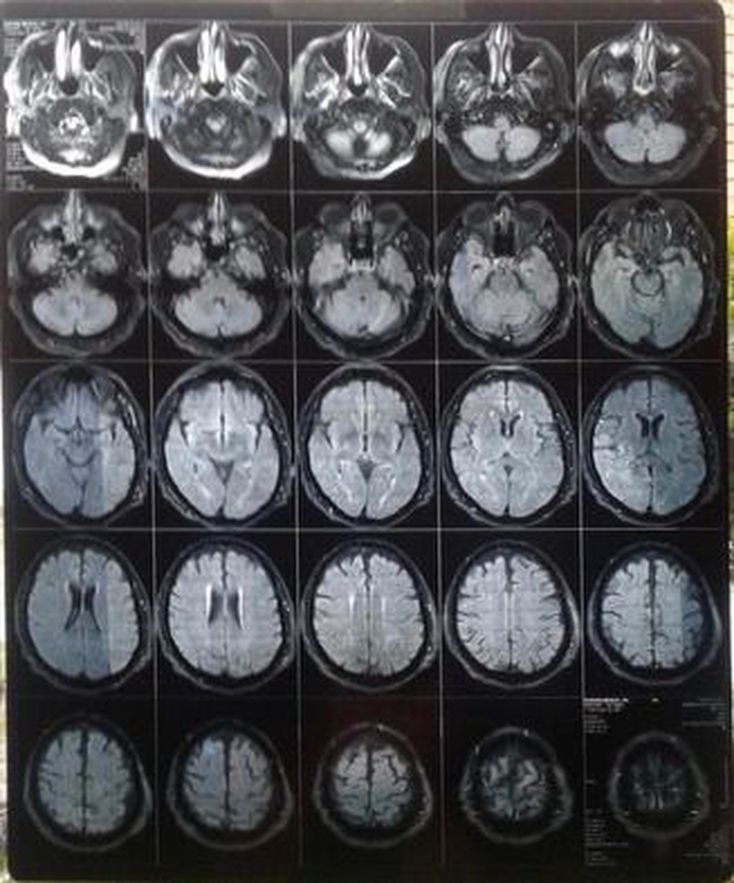

Patient has demonstrated cognitive decline. Feedback please

Brain

Mri

Cognitive